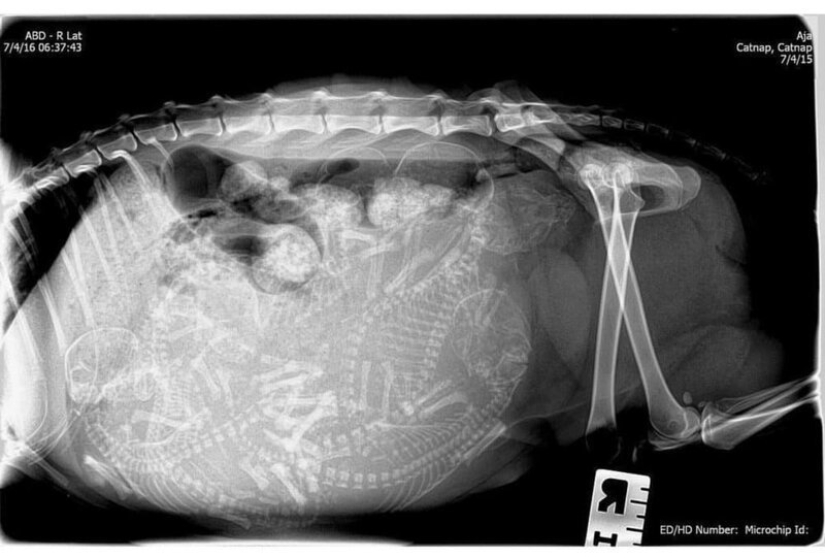

gata preñada